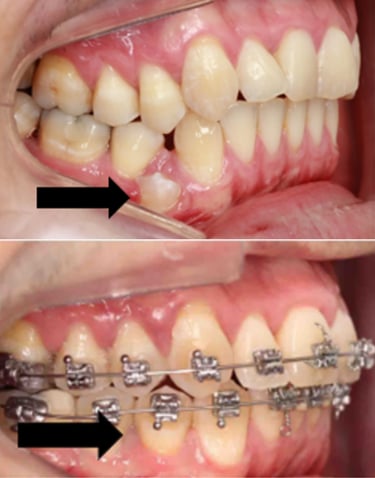

EVOLUÇÃO